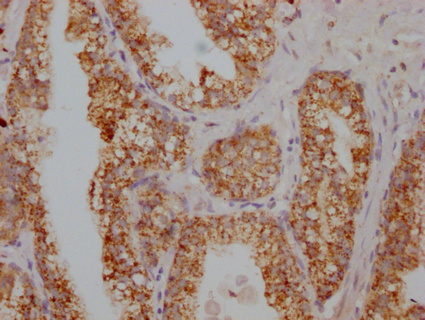

IHC image of CSB-PA020626HA01HU diluted at 1:100 and staining in paraffin-embedded human prostate cancer performed on a Leica BondTM system. After dewaxing and hydration, antigen retrieval was mediated by high pressure in a citrate buffer (pH 6.0). Section was blocked with 10% normal goat serum 30min at RT. Then primary antibody (1% BSA) was incubated at 4°C overnight. The primary is detected by a Goat anti-rabbit IgG labeled by HRP and visualized using 0.05% DAB.